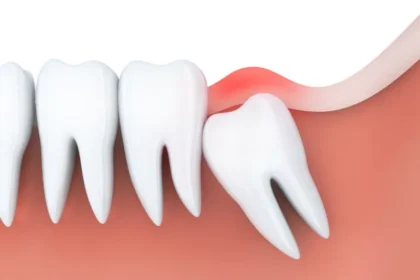

親知らずは横に傾いたり、埋まったまま出てこない場合が多く、手前の歯までむし歯になったり、歯ぐきが腫れたりしてトラブルの原因になってしまいます。親知らずはまっすぐ生えている場合には通常の抜歯で対応できますが、横向きに生えていたり、歯ぐきや骨に埋まっていたりする場合は、歯科口腔外科での処置が必要になります。当院ではCTを活用した精密な診断により、神経や血管の位置を把握したうえで、必要に応じて大学病院などの高度医療機関と連携しながら、安全性に配慮した抜歯を行います。

親知らずは、生え方によってさまざまなトラブルを引き起こします。横向きや斜めに生えてくると、痛みや腫れを感じることがあり、歯ぐきの一部に埋まったままの状態でも同じような症状が出ることがあります。

親知らずがまっすぐに生えておらず、斜めや横向きに生えていると、歯ぐきとの間に汚れがたまりやすくなり、むし歯や歯周病の原因になります。また、隣の歯を押すことで歯並びが乱れたり、他の歯の根が圧迫されてダメージを受けたりすることもあります。